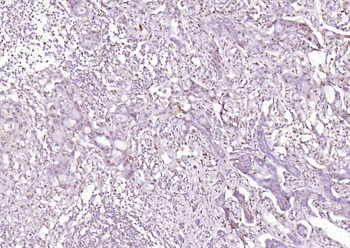

50 μl, 100 μl, 25 μl - CD14 Recombinant Rabbit Monoclonal Antibody [orb608064]Featured

IF, IHC-Fr, IHC-P, WB

Human

Rabbit

Recombinant

Unconjugated

100 μl, 50 μl, 25 μl - Rad51 Recombinant Rabbit Monoclonal Antibody [orb608069]Featured